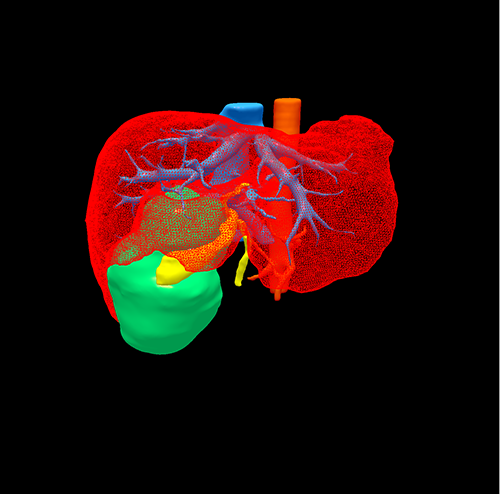

右肝胆管囊腺瘤----S5囊腺瘤切除、胆囊切除